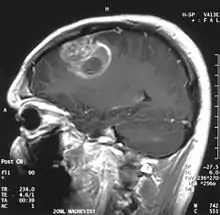

![]() | |

| Coronal MRI with contrast of a glioblastoma in a 15-year-old male | |

When viewed with MRI, glioblastomas often appear as ring-enhancing lesions. The appearance is not specific, however, as other lesions such as abscess, metastasis, tumefactive multiple sclerosis, and other entities may have a similar appearance.[58] Definitive diagnosis of a suspected GBM on CT or MRI requires a stereotactic biopsy or a craniotomy with tumor resection and pathologic confirmation. Because the tumor grade is based upon the most malignant portion of the tumor, biopsy or subtotal tumor resection can result in undergrading of the lesion. Imaging of tumor blood flow using perfusion MRI and measuring tumor metabolite concentration with MR spectroscopy may add diagnostic value to standard MRI in select cases by showing increased relative cerebral blood volume and increased choline peak, respectively, but pathology remains the gold standard for diagnosis and molecular characterization.